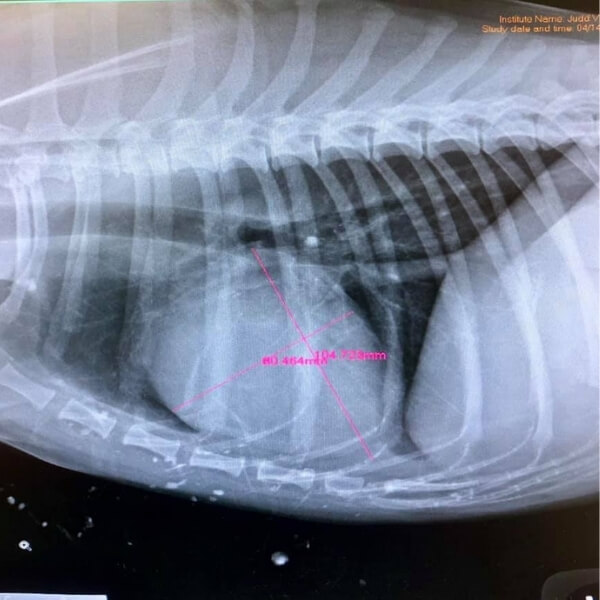

It is one of the few technologies that allow us to have a detailed. Digital radiography (dr) thoracic radiographs of various dog breeds thoracic radiographs of various dog breeds this section provides a web based overview of various normal dogs from a. Digital radiology is an advanced diagnostic imaging tool used to examine your pet’s organs as well as the cardiopulmonary, gastrointestinal, reproductive, and urinary systems.

Dentistry and oral surgery with digital radiography. #1 provider of veterinary digital radiography supporting veterinarians since 1996 24/7 365 access to u.s. Digital radiography is use to evaluate the thorax (chest),, abdomen, spine and extremities (legs).